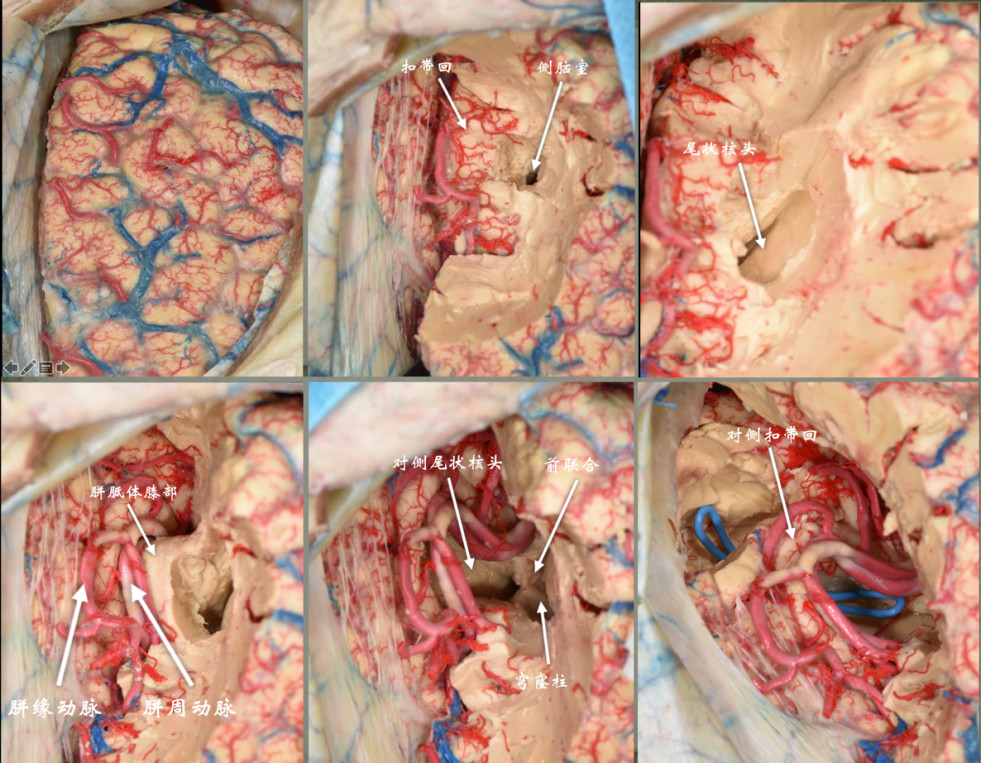

入院后完善术前常规准备,在全麻行左额开颅切除肿瘤。左侧额叶累及范围较大,所以选择左侧入路,为便于显露胼胝体等中线结构,骨瓣达中线。切除额叶部分肿瘤后沿纵裂分离肿瘤与胼缘动脉和胼周动脉的粘连,显露同侧扣带回和胼胝体,打开左侧侧脑室,定位尾状核头、室间孔等重要结构,进一步切除肿瘤。尾状核头表面及核团内部富含血管,形状和高级别胶质瘤容易混淆,因此术中确定尾状核头十分重要(图2)。予手术全切肿瘤。

图2. 手术切口如左图示,左额开颅,虚线为骨瓣范围,中间达中线;中图所示为左额部分肿瘤切除减容后沿大脑镰显露胼缘动脉及扣带回、胼胝体。左图为打开左侧脑室额角,定位尾状核头、室间孔。图中可见尾状核头表面布满血管,类似“草莓”,这是尾状核头的特点。室间孔后上方的粗大血管为透明隔静脉。

4)手术中注意胼胝体膝部下方皮层及深部核团的保护(图5)。

图5. 右侧入路切除累及双侧额叶和胼胝体的蝴蝶形肿瘤的解剖图谱:后首先沿大脑镰切除部分肿瘤获得显露空间,分离显露同侧胼缘动脉和扣带回,继续线路胼胝体并向外侧进入侧脑室额角,定位胼胝体膝部、尾状核头、室间孔等重要解剖结构,进而判断穹窿、前联合、伏隔核等重要结构的位置,确定肿瘤切除的范围。切除同侧额叶肿瘤及累及胼胝体肿瘤后进入对侧侧脑室,定位对侧扣带回、尾状核头,如肿瘤侵犯对侧额叶较多,可对侧额叶内侧皮层造瘘切除额叶深部病变,注意保护对策扣带回及深部白质纤维。